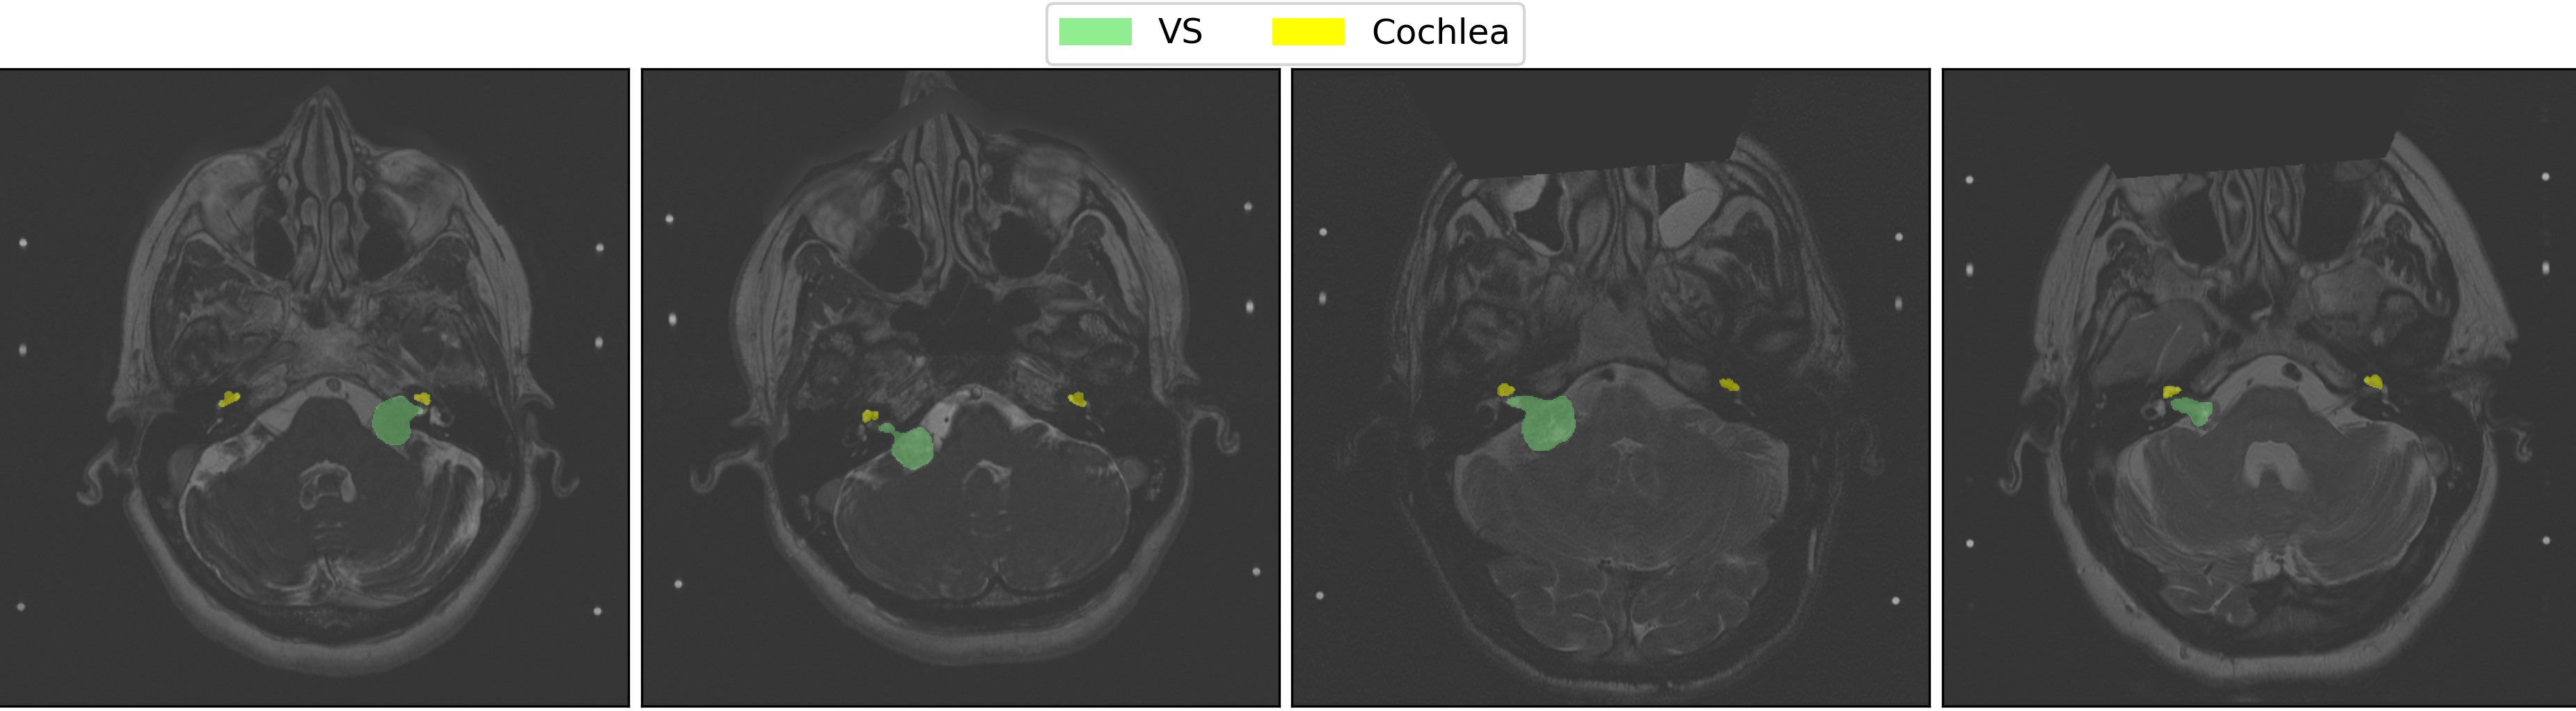

The results of our method on the validation dataset are presented in Table. 1. With a mean Dice score of 0.826, our method secures a top-10 finish in the CrossMoDA 2022 competition. Fig. 3 highlights some qualitative results produced by our method on the validation set. Finally, our method ranked 5th in the test phase of the crossMoDA 2022 challenge with a mean Dice score of 85.65%, and ranked in 3rd place for the Vestibular Schwannoma segmentation with a mean Dice score of 86.7%.